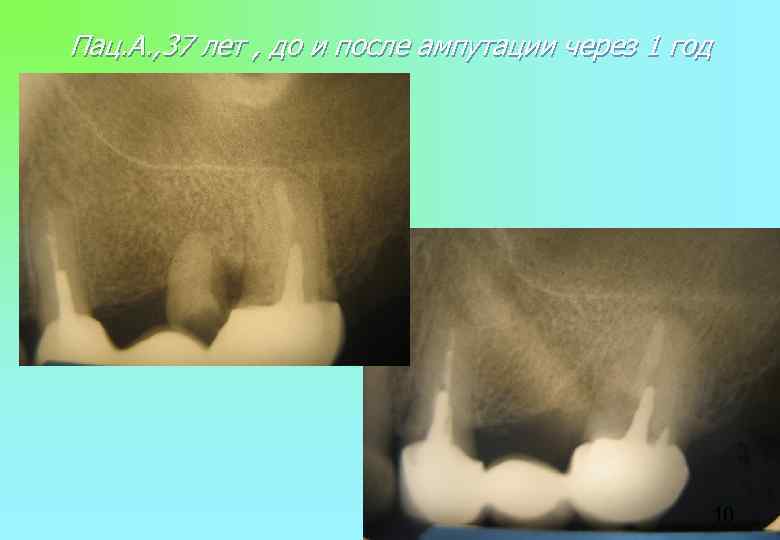

Пац. А. , 37 лет , до и после ампутации через 1 год 10 Пац. А. , 37 лет , до и после ампутации через 1 год 10